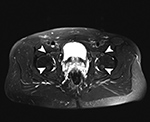

Pulsation Artifact. Axial T2-weighted fat-saturated MR image of the pelvis demonstrates femoral artery pulsation resulting in ghost images (arrowheads) obscuring the anterior labra and simulating femoral head lesions bilaterally.